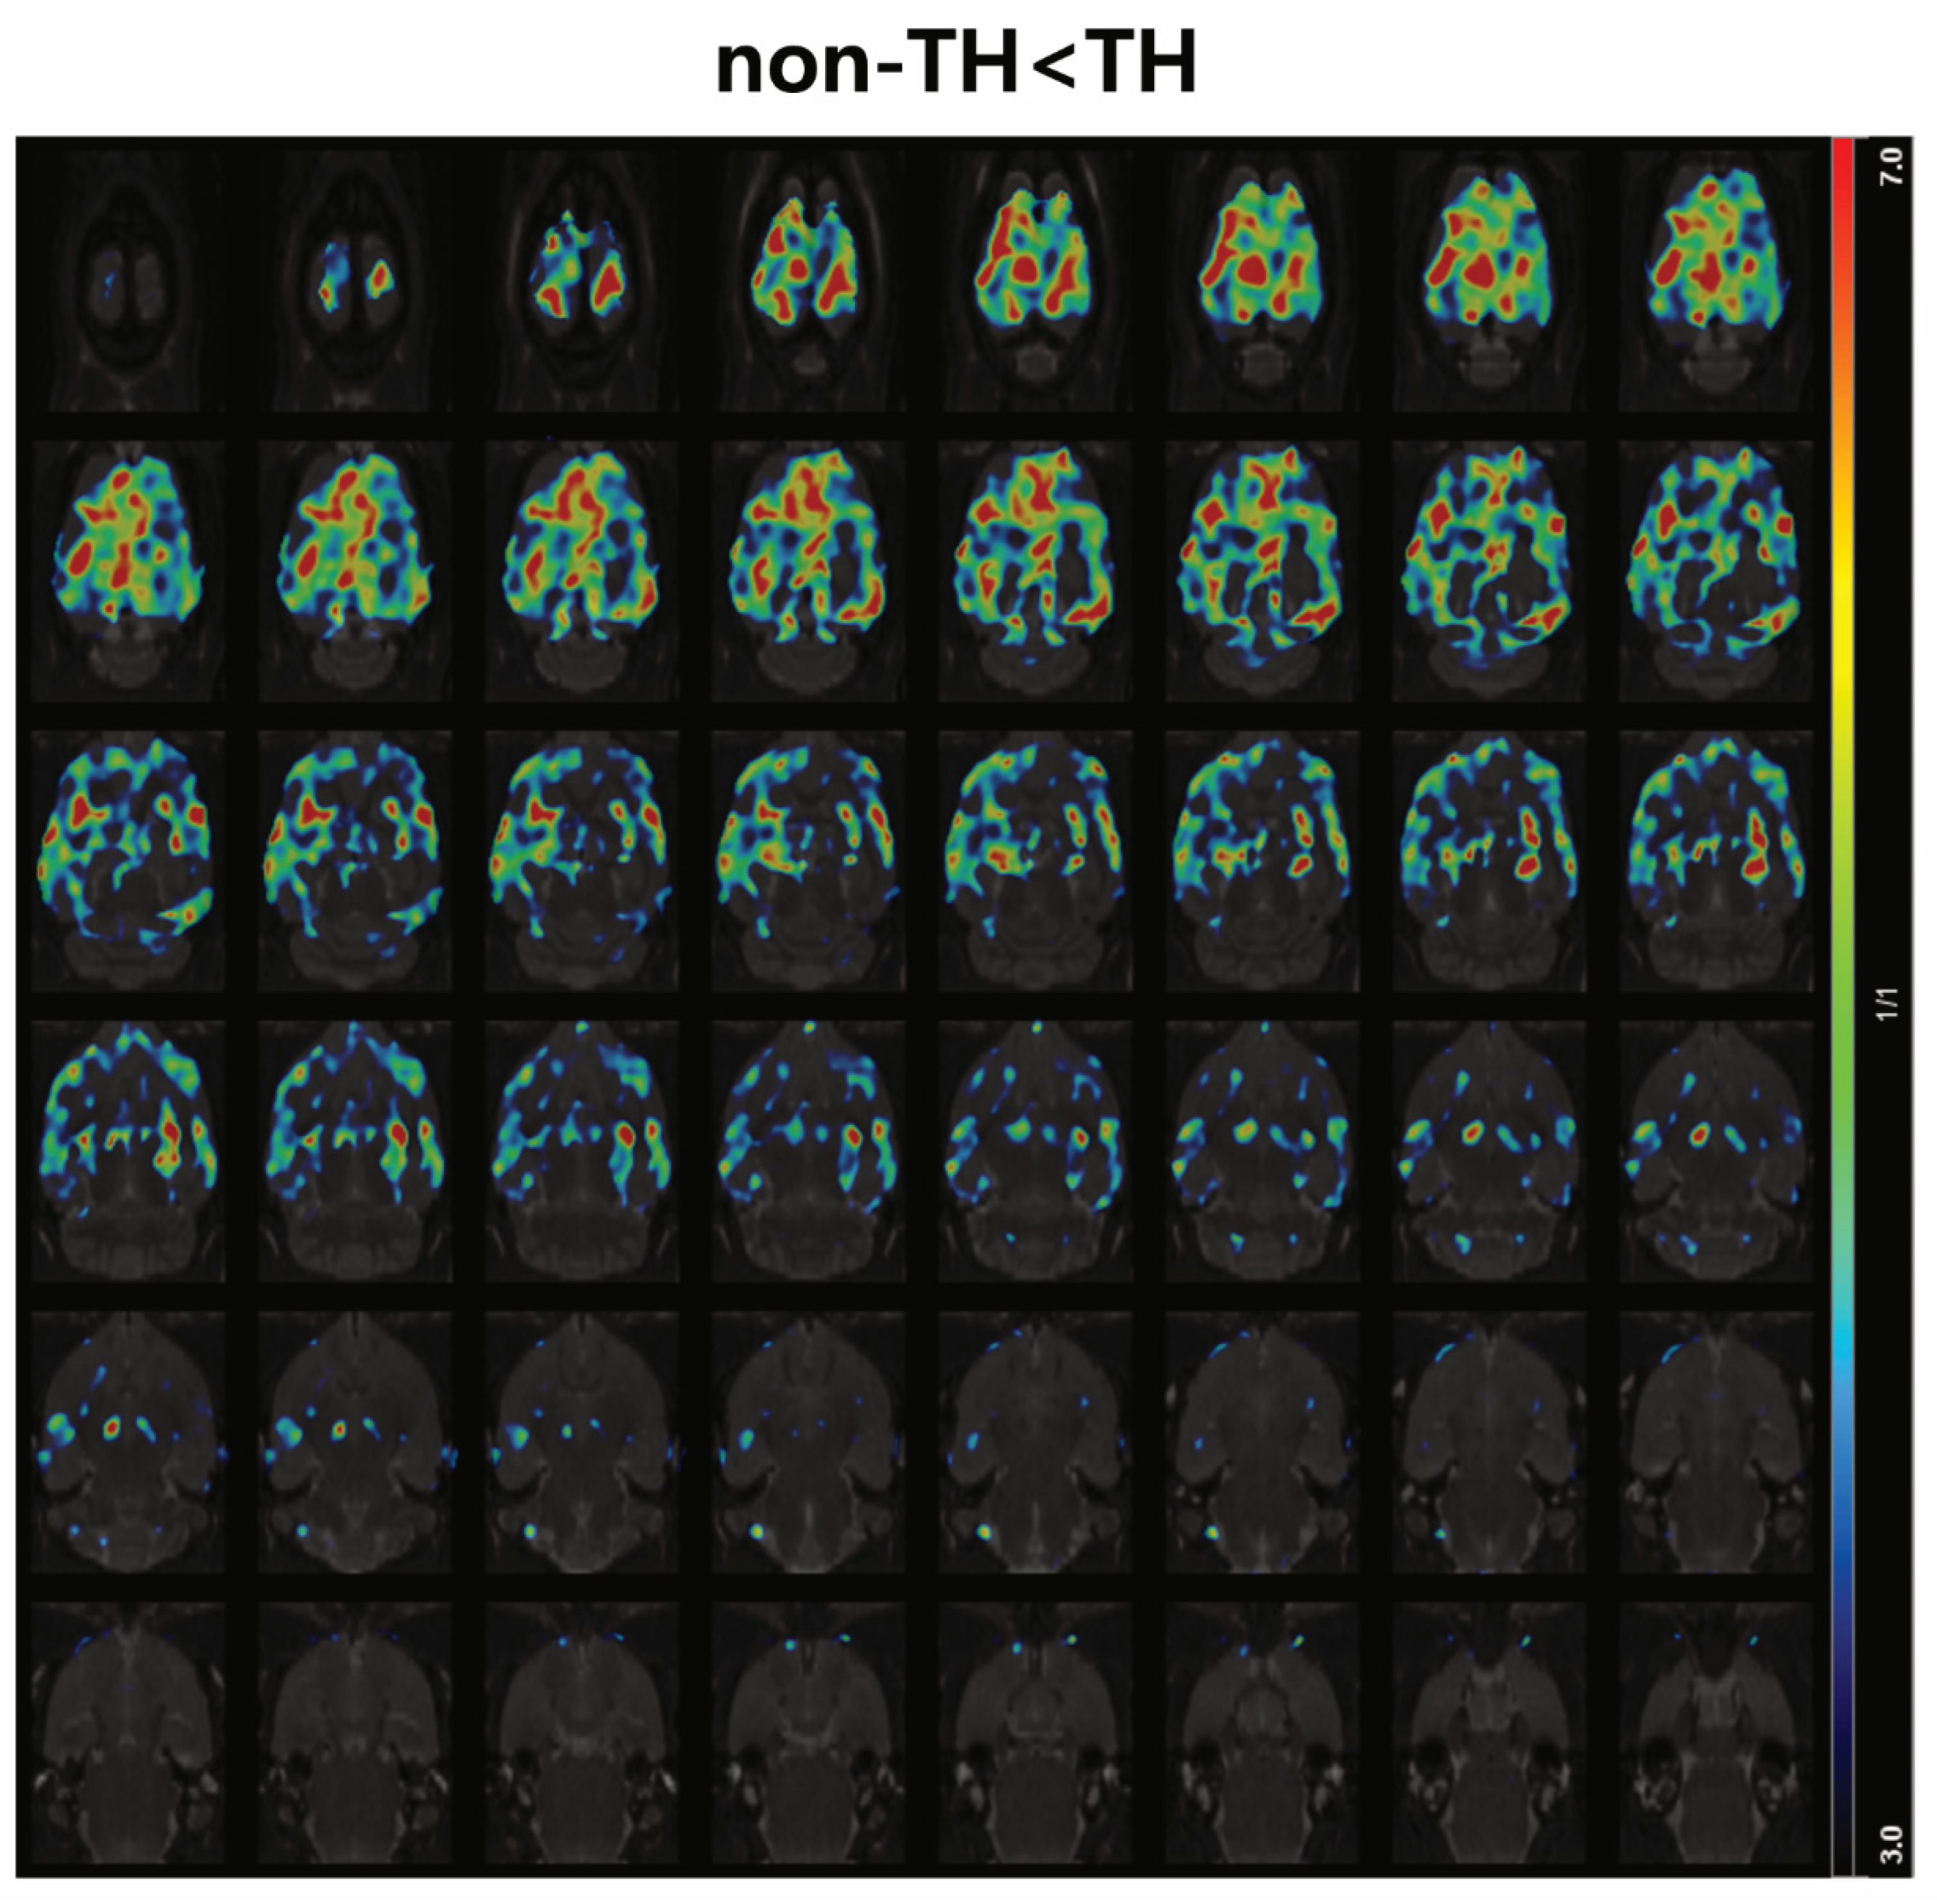

3.3. Distribution of Regional 18F-FDG Uptake According to the Application of TH

3.3.2. Subgroup Analysis: Survived Group

3.3.3. Subgroup Analysis: Non-Survived Group